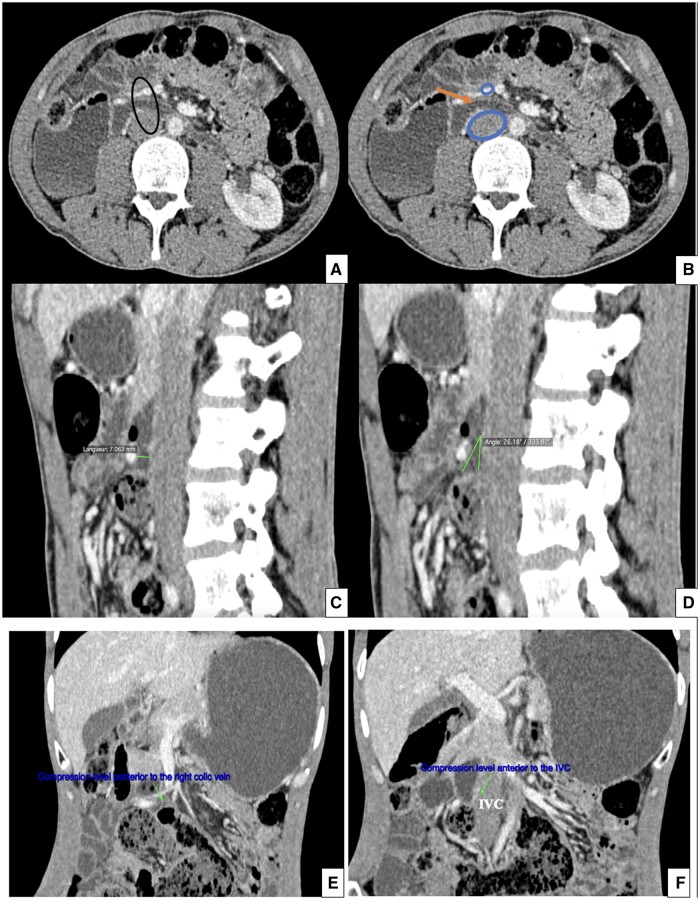

Superior mesentery artery (SMA)-like syndrome is an increasingly used term to describe vascular compression of the third duodenal portion between structures other than the superior mesenteric artery and aorta. Although rare, this clinical condition is as serious as true SMA syndrome and requires similar management. However, the diagnostic criteria are not well established yet and require a case-by-case analysis, including a review of various clinical symptoms, especially evolving ones, as well as radiological imaging and effectiveness of conservative therapeutic manoeuvres. The presented case involves a double vascular compression in a 50-year-old woman with no medical history, one of which is between 2 venous structures. The patient had been experiencing recurrent abdominal pain, vomiting, and distension for a long time. Laboratory tests were normal, and gastroesophageal endoscopy revealed Barrett's oesophagus. CT-enterography revealed 2 duodenal vascular compressions. Dietary measures were initiated with close follow-up. To the best of our knowledge, this is the first reported case in the world literature and adds to the existing body of SMA-like syndromes.